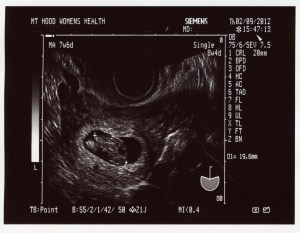

Surprise! February 21, 2012 by Dawn Marie Leave a comment Introducing our new family member! Due mid-Sept of 2012 Share this: Share on Facebook (Opens in new window) Facebook Share on Pinterest (Opens in new window) Pinterest Share on X (Opens in new window) X Share on Tumblr (Opens in new window) Tumblr More Email a link to a friend (Opens in new window) Email Share on Reddit (Opens in new window) Reddit Share on LinkedIn (Opens in new window) LinkedIn Print (Opens in new window) Print Like Loading... Related